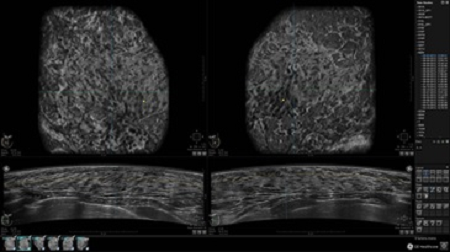

• Многооконный просмотр: 4 - 12 изображений

• Одновременный просмотр двух изображений для сопоставления в коронарной плоскости

• Стандартизованная ориентация изображения: «толстый срез» в коронарной плоскости; поперечная; сагиттальная плоскость; радиальный и антирадиальный поворот изображения; просмотр исключительно области интереса